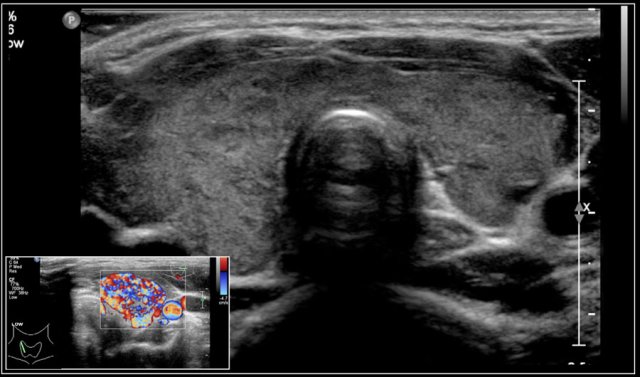

Here an image of a 16-year-old girl with hyperthreoidism.

A diffusely enlarged thyroid gland is seen with hyperemia.

The final diagnosis was Graves disease.

On color doppler the blood flow is often normal but can be increased like in Graves' disease.

In Graves disease the thyroid gland is also enlarged and shows an increased perfusion.

On color Doppler it has been described as an inferno in red and blue.